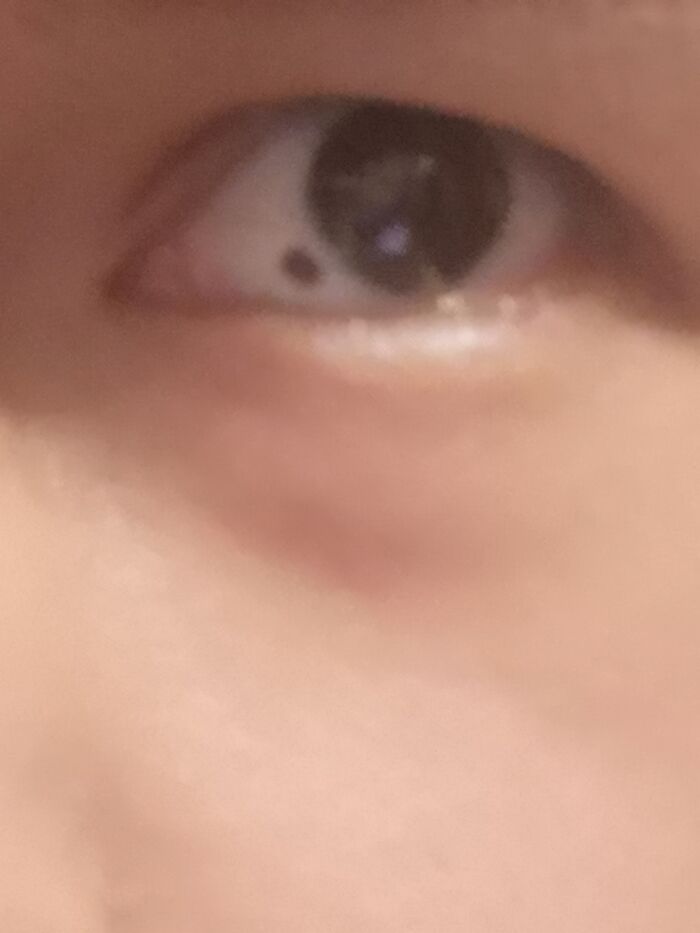

I have a body mole in my eye, like inside of it and near the pupil

Legacy_of_Zero , Legacy_of_Zero (the actual photo) Report